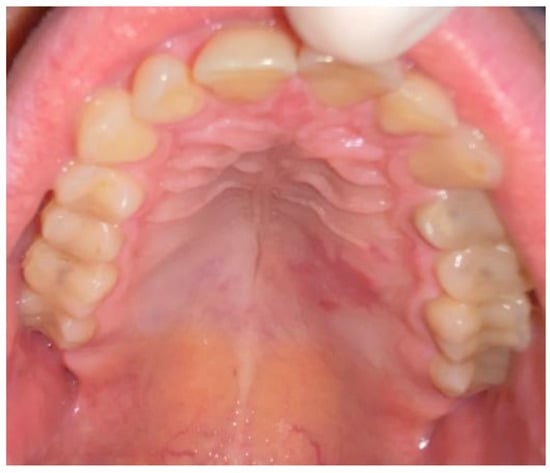

2. Case Description